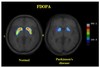

Pathologies associées aux NGC ? quoi ? quels sont les symptômes de cette maladie ?

* La maladie de Parkinson (1% de la population au-dessus de 50 ans). * Symptômes de la maladie de Parkinson: ----» Hypokinésie, réduction considérable de la capacité de réalisation des mouvements: - Bradykinésie (mouvements volontaires lents). - Akinésie (difficultés à initier certains mouvements musculaires). - Rigidité. - Tremblements.